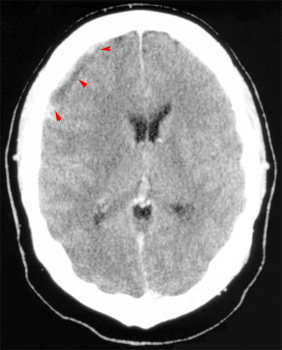

Question 7: Given the following head CT, the most likely diagnosis is: